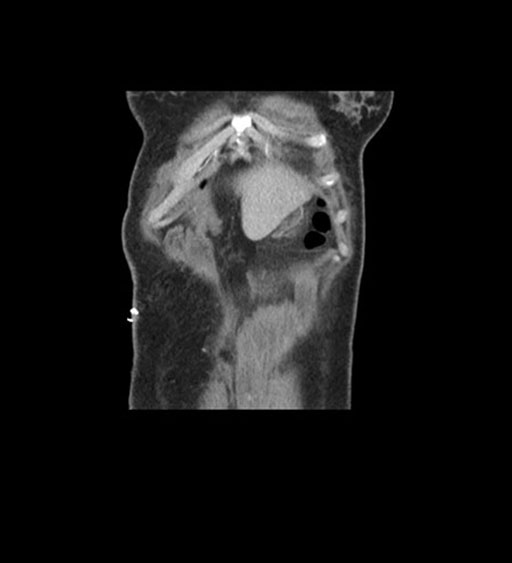

Imaging Analysis

Look through the patient's CT scan to identify any areas of concern for the necessary procedure.

Coronal Arterial

Coronal Venous

Based on initial findings, which issue(s) would you be most concerned about?